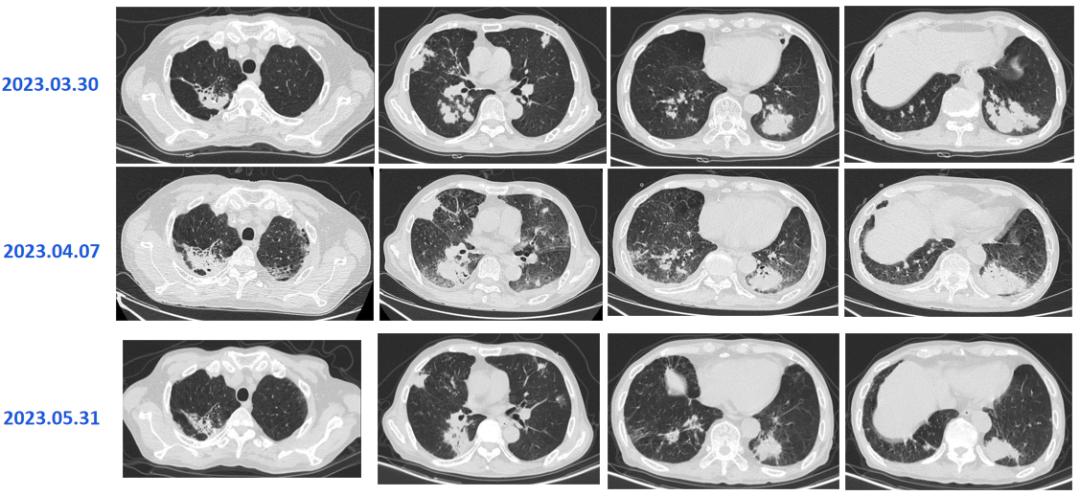

2022-7-13胸部CT

临床病例(三):甘某某,男,50岁,2022年7月12日因「发热,、咳嗽、咳痰、气喘10余天,加重2天」入院。痰色白不易咳出,体温最高38.5℃。外院予「莫西沙星+头孢他啶」抗感染,「甲强龙40mg」抗炎,仍反复发热,2天前咳嗽、咳痰、气喘加重。

既往史及个人史:2022年2月于广西省人民医院行「肾移植术」,后规律服用「吗替麦考酚酯胶囊、他克莫司」抗排斥。

查体:T 37.3℃,P 118次/分,R 25次/分,BP 118/89mmhg。双肺呼吸音粗,未闻及干湿性啰音和胸膜摩擦音。心腹查体未见明显异常。

血气分析:PCO2:26.9mmHg↓、PO2:56.2mmHg↓、实际碳酸氢根17.2mmol/L↓、标准碳酸氢根19.8mmol/L↓、总CO2:40.5mmol/L↑、实际剩余碱-5.4mmol/L↓、标准剩余碱-6.4mmol/L↓、氧饱和度88.9%↓、氧合血红蛋白86.6%↓、还原血红蛋白10.8%↑、P50:26.55↓。

血常规:白细胞 8.22X10^9、粒细胞百分比 85.1%↑、粒细胞计数 7.65X10^9↑、淋巴细胞百分比 7.4%↓、淋巴细胞计数 0.45X10^9↓、嗜酸性细胞百分比 0%。

CRP:106mg/L↑

诊治经过如下:

患者既往有肾移植病史,使用激素及免疫*制剂抑**,此次肺炎病情进展迅速,胸部CT影像学符合PJP或巨细胞病毒改变,需立即给予PJP及更昔洛韦诊断性治疗,并积极完善纤维支气管镜肺泡灌洗明确病原菌。

2022年7月14日的BALF-mNGS结果,检出耶氏肺孢子菌。

患者的呼吸道病原体谱抗体,EB病毒、巨细胞病毒DNA,肺炎支原体,T-SPOT,术前四项均未见异常。

2022年7月17日:患者气喘较前明显好转,改口服SMZ;7月18日:复查胸部CT。患者仍有活动性气喘,暂续前治疗;7月20日:气喘明显加重,急查血气;7月22日:炎症指标上升,转ICU行气管插管+呼吸机辅助呼吸,CRRT。

2022年7月18日,患者胸部CT见双肺间质性炎症范围较前扩大,考虑PJP感染导致的间质性炎症持续渗出。

患者属重症PJP,给予静脉使用SMZ注射液病情一度好转,但因经济原因,改为口服SMZ治疗,后病情进展迅速。

2022年7月24日,BALF-mNGS检出耶氏肺孢子菌、肺炎克雷伯菌。肺炎克雷伯菌系院内感染。7月28日,多次复查血常规提示血小板进行性下降;8月8日:抗生素降阶梯;8月10日:气管插管2周,暂难脱机,需行气管切开,血小板低,输注血小板,择期行气切;8月13日:血小板进行性下降,感染消耗可能。血小板27X109/L、CRP89.2mg/L;8月16日:复查血常规示三系进行性下降,降钙素原升高15.6ng/ml,感染加重;8月17日:炎症指标较前明显升高,调整抗生素。血小板16X109/L、CRP272mg/L;8月18日:患者深昏迷,FIO2100%,血氧饱和度波动于60%-80%,去甲肾上腺维持血压,随时可能出现死亡风险,患者家属强烈要求出院,劝阻无效,予办理自动出院。血小板11X109/L、CRP326mg/L。

从该例病例,我们可以看到,PJP的早期诊断和治疗非常关键,及时早期使用SMZ的治疗对预后起着决定性的作用,对于重症PJP,建议尽早使用SMZ注射液,并序贯口服治疗。